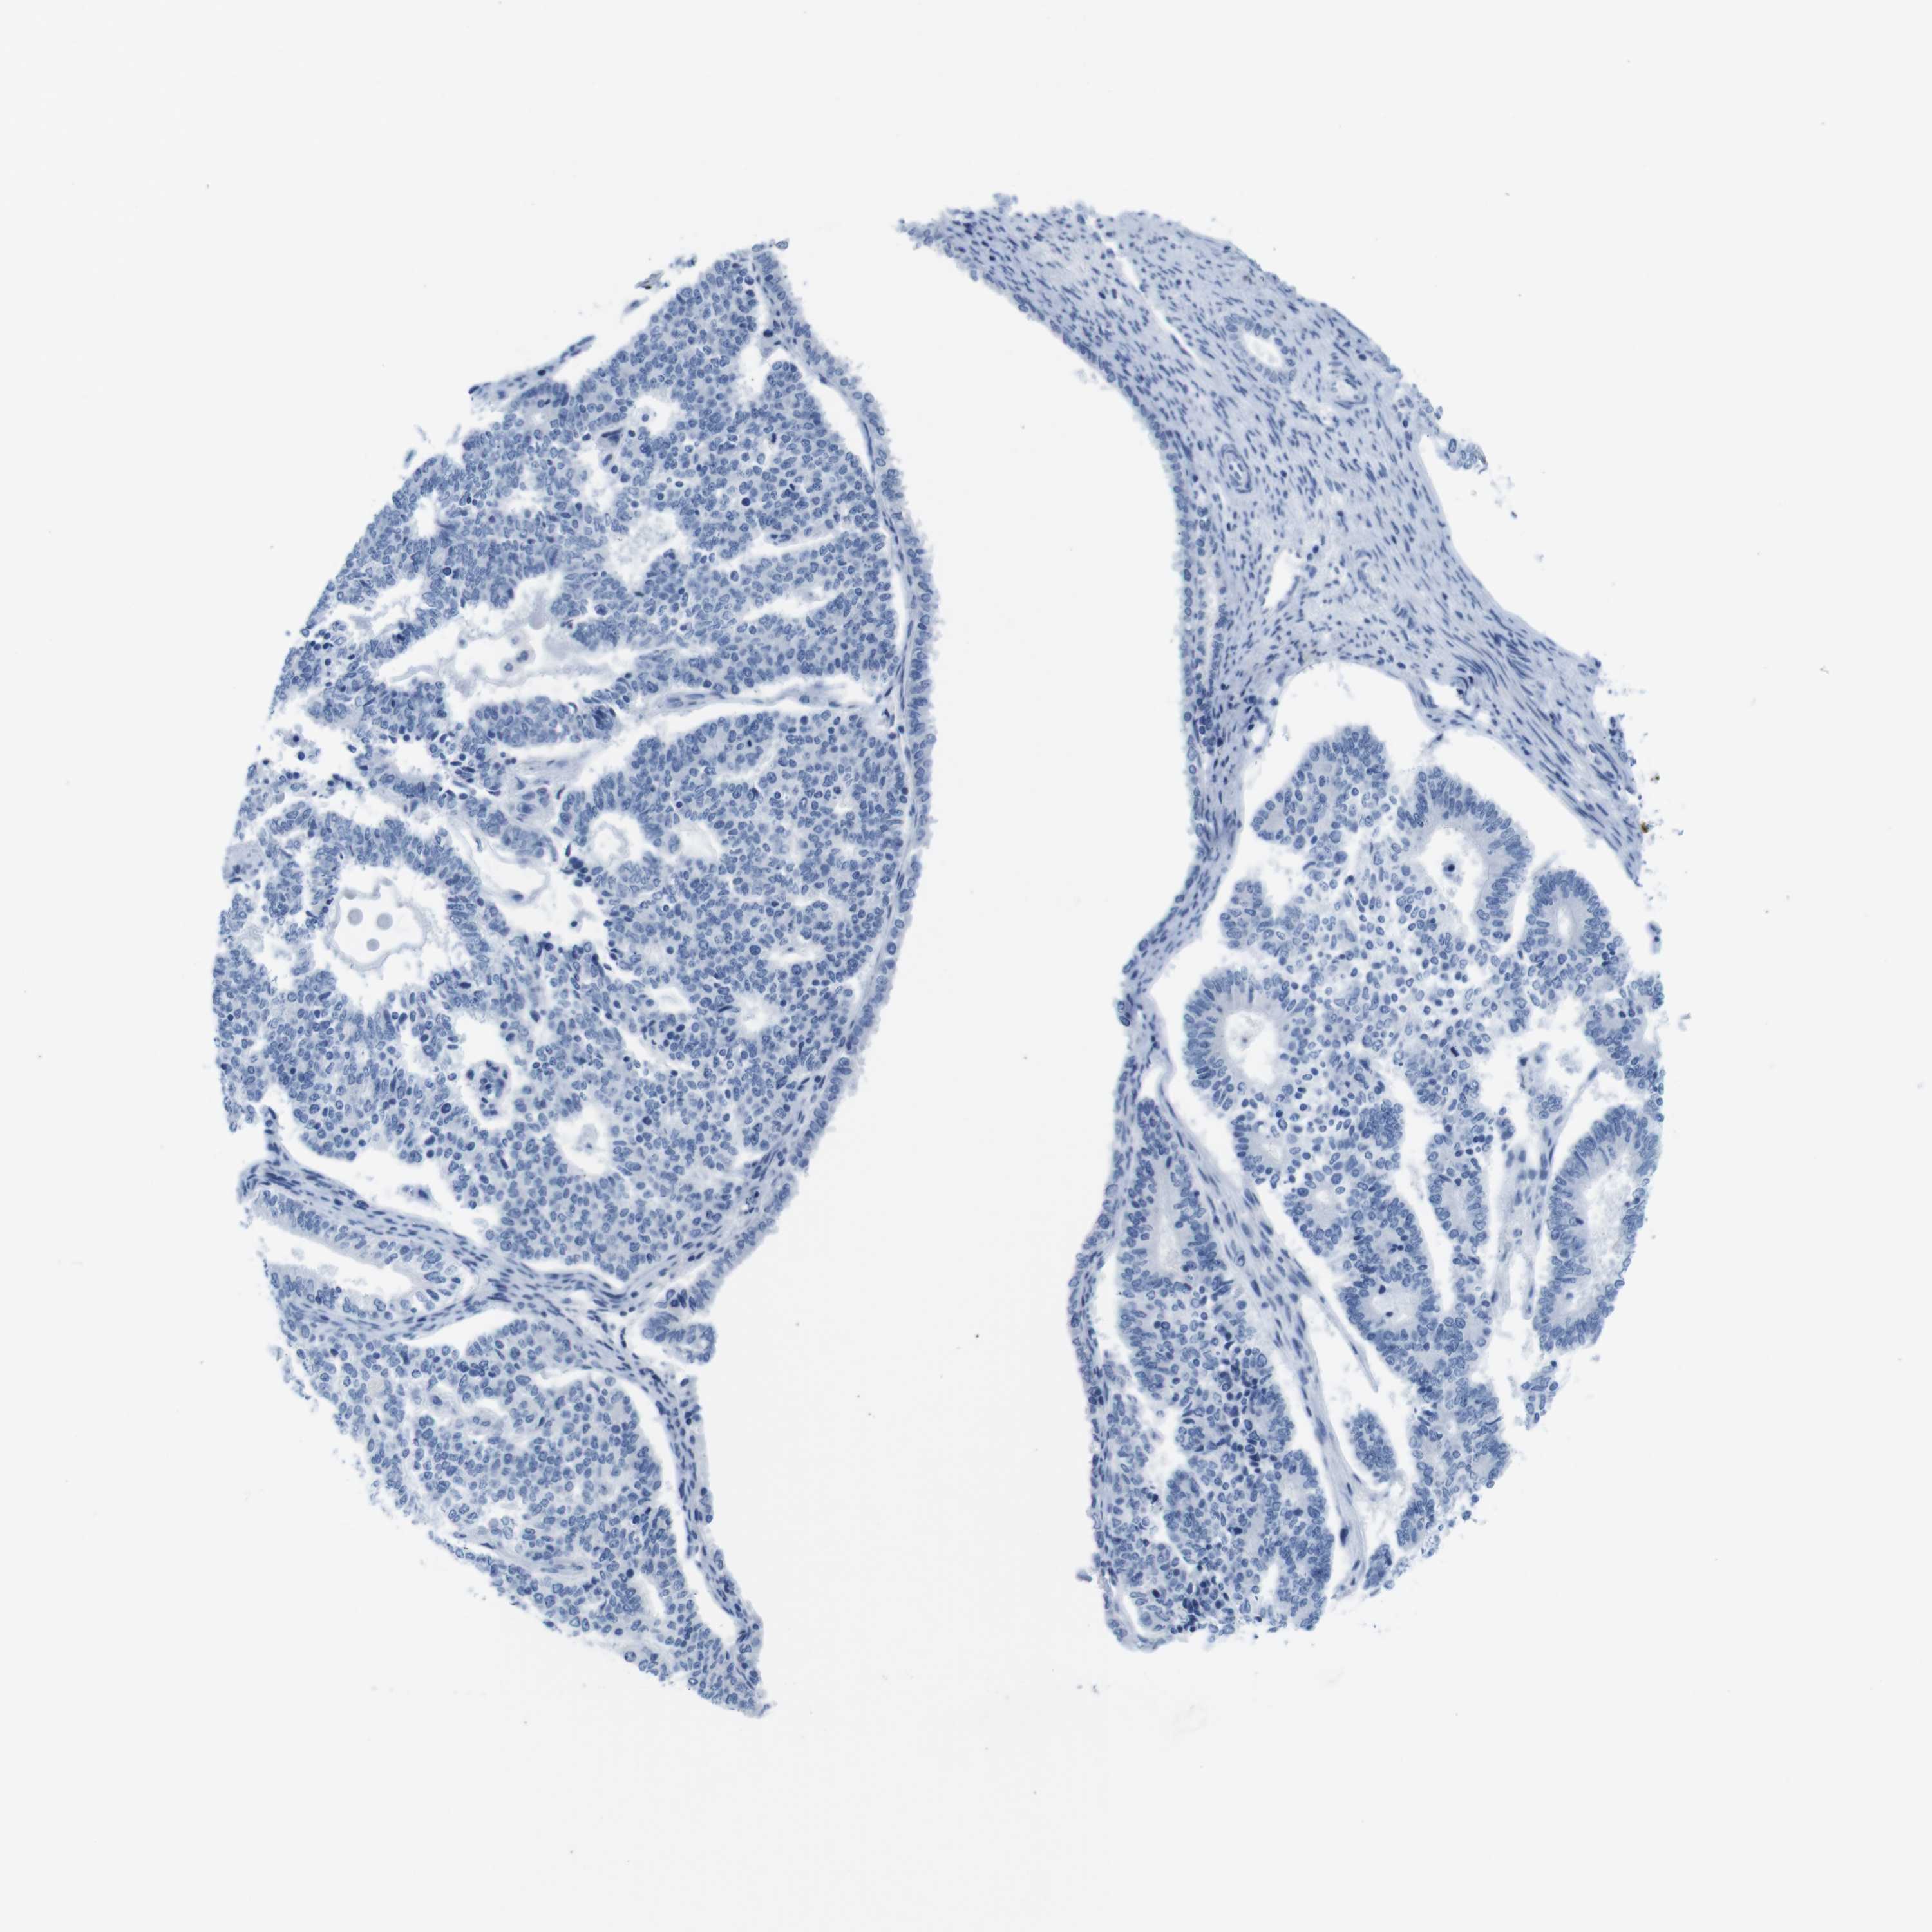

ENDOMETRIAL CANCER - Protein expressioni

A mouse-over function shows sample information and annotation data. Click on an image to view it in a full screen mode. Samples can be filtered based on level of antibody staining by selecting one or several of the following categories: high, medium, low and not detected. The assay and annotation is described here.

Note that samples used for immunohistochemistry by the Human Protein Atlas do not correspond to samples in the TCGA dataset.

Antibody stainingi

Antibody staining in the annotated cell types in the current human tissue is reported as not detected, low, medium, or high, based on conventional immunohistochemistry profiling in selected tissues. This score is based on the combination of the staining intensity and fraction of stained cells.

Each image is clickable and will lead to virtual microscopy that enables deeper exploration of all samples and also displays staining intensity scores, fraction scores and subcellular localization as well as patient and tissue information for each sample.

Antibody HPA039061

Antibody HPA039062

Antibody CAB015442

Antibody CAB022600

Staining

High

Medium

Low

Not detected

Intensity

Strong

Moderate

Weak

Negative

Quantity

>75%

75%-25%

<25%

None

Location

Nuclear

Cytoplasmic/membranous

Cytoplasmic/membranous,nuclear

Adenocarcinoma, NOS